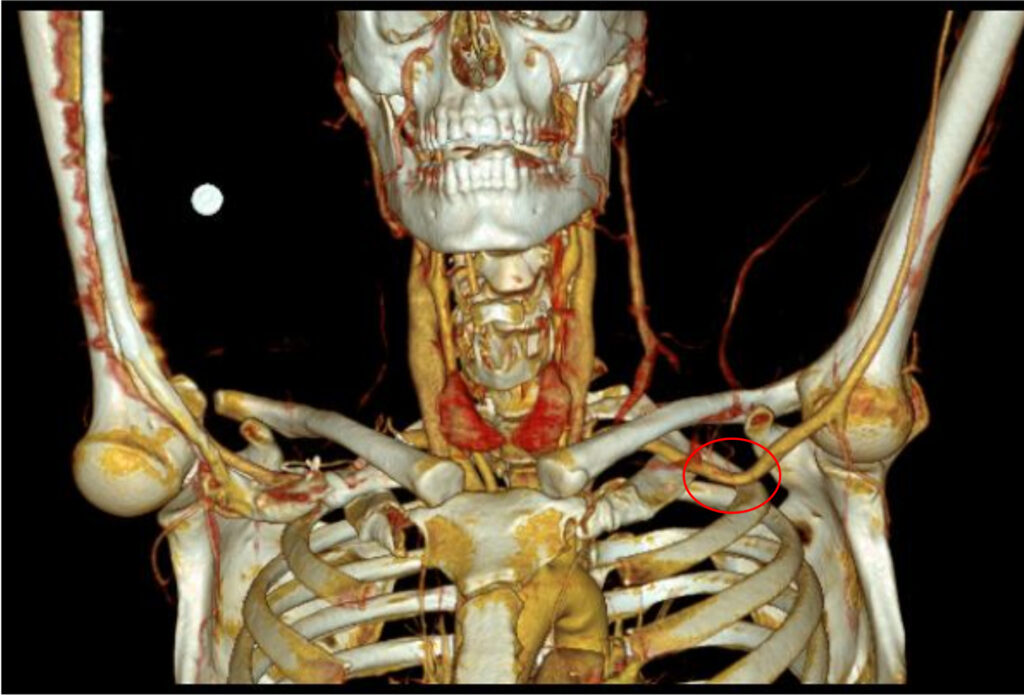

25-jährige Fußballerin mit belastungsinduzierten drückenden und krampfartigen Wadenschmerzen beidseits (linksbetont, Crescendo und Decrescendo des Schmerzes innerhalb von Sekunden) nach Laufstrecken von 2 ½ km. In der Vergangenheit wurde ein Logensyndrom der tiefen Wadenflexoren diagnostiziert und endoskopisch-assistiert gespalten. Dies, sowie rezidivierende intramuskuläre Botulinumtoxin-Injektionen in die Wadenmuskulatur haben keine anhaltende Beschwerdelinderung herbeiführen können.

Im Gegensatz zum belastungsinduzierten chronischen Kompartmentsyndrom zeigt sich beim Entrapment-Syndrom der Arteria poplitea eine belastungslimitierende Schmerzentwicklung innerhalb weniger Sekunden, welche sich nach Sistierung der Belastung auch ebenso schnell wieder verflüchtigt. Dementsprechend ist die Demaskierung eines Kompressionssyndroms der Arteria poplitea mittels Knöchel-Arm-Index nach Laufbandbelastung oft schwierig, bzw. nicht selten falsch-negativ. Eine Duplexsonographie der Kniekehlenarterie in Bauchlage unter entsprechender Provokation in Plantarflexion kann hierbei meist zielführend sein. Eine anschließende CT-/MR-Angiographie (ebenfalls unter Provokation) dient dem behandelnden Gefäßchirurgen dann zur besseren Visualisierung der Anatomie im Bereich der Fossa poplitea. Am häufigsten zeigt sich hierbei eine Kompression der Arteria poplitea durch den medialen Musculus gastrocnemius.

Die Inzidenz eines poplitealen Entrapments mit anatomischem Korrelat in der Fossa poplitea befindet sich bei rund 0,6 – 3,5 %. Nicht selten findet sich duplexsonographisch jedoch eine Kompression der Kniekehlenarterie im Bereich der Soleus-Schlinge ohne eigentliche anatomische Variationen, was als funktionelles Entrampent definiert wird und primär konservativ behandelt werden sollte. Liegt hingegen eine anatomische Anomalie vor ist die offen-chirurgische Dekompression mi-t Myektomie (meist des medialen Musculus gastrocnemius) die Therapie der Wahl [5].